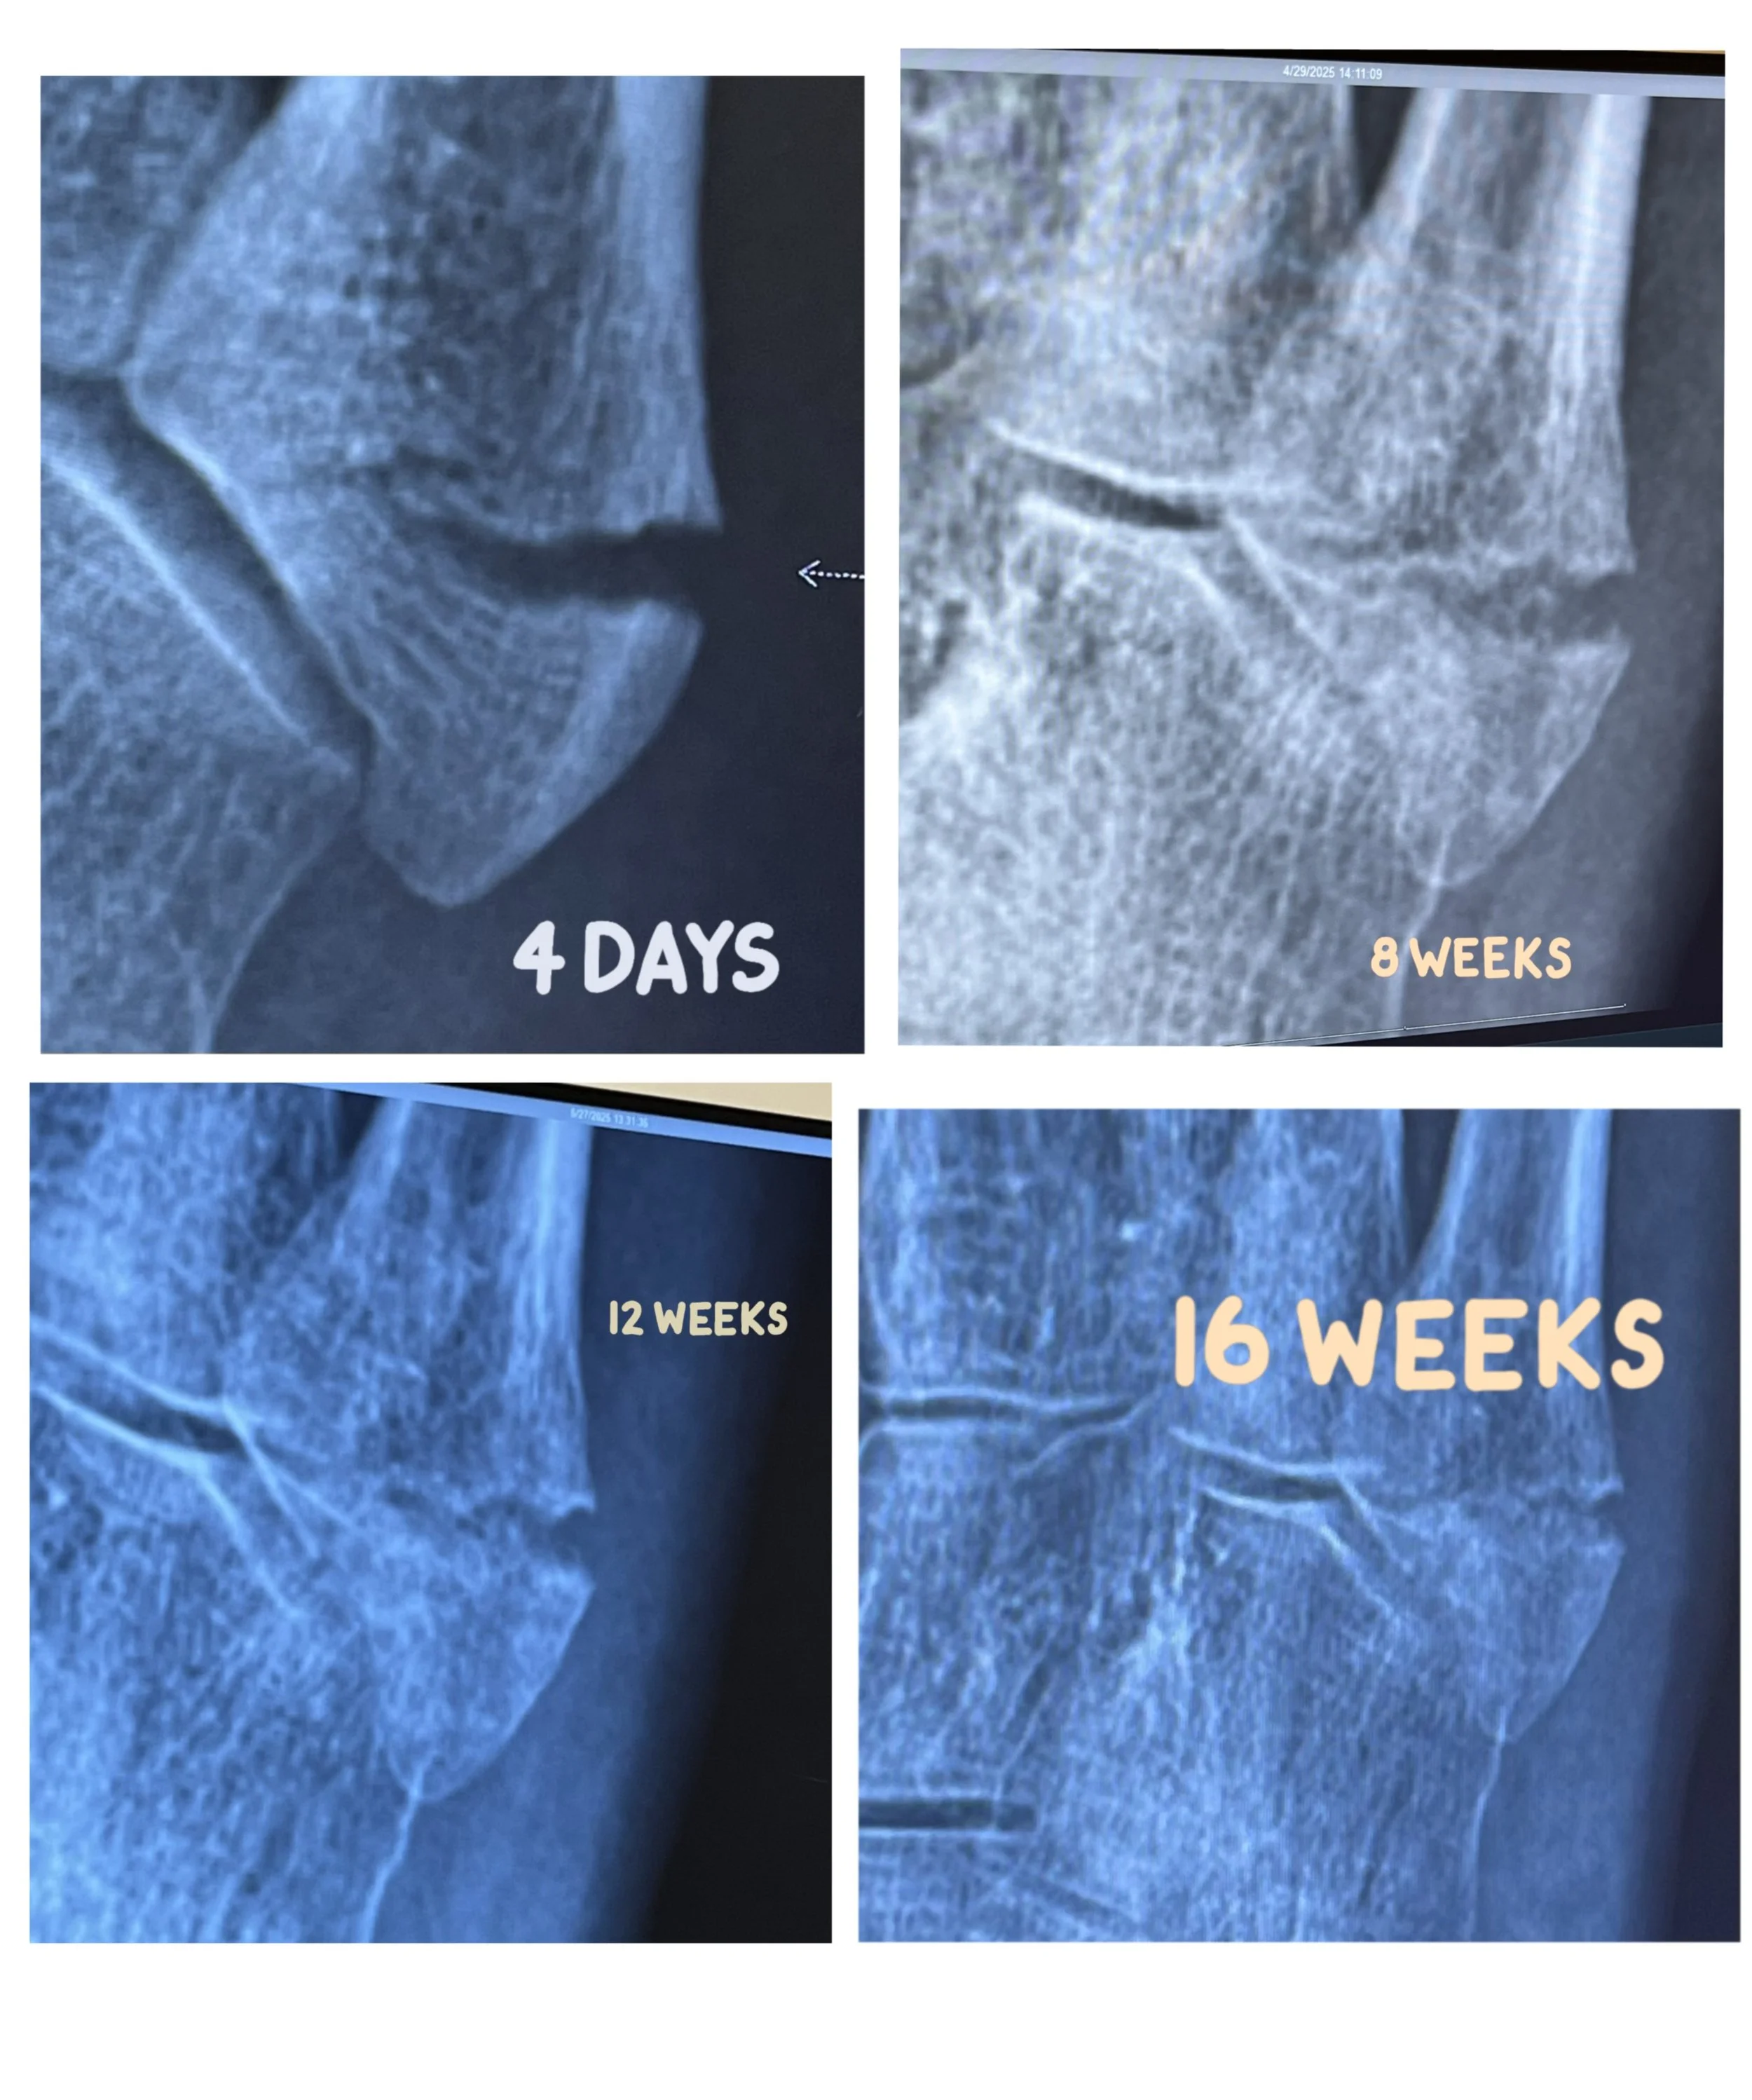

Apr 29 (Day 58) So nervous about getting the x-rays and also feeling stronger. Doing more. Didn’t take crutches in to the appointment and then had to stand for the x-rays. And… the x-rays didn’t show enough bone growth so 4 more weeks in the boot. Full-time, still sleeping in it. So sad. Also saw another fracture we couldn’t see in the original x-rays that has some bone growth. Vacillating between wallowing and looking for opportunity. Steps: 5335

May 27 (Day 86) 12-week x-ray, not enough progress. Very sad. I’ve also now lost a lot of bone density and need to walk more outside without the crutches. So confusing. Trying to stay positive. I was told I could purchase an EOS brace and carbon fiber plate if I wanted to do anything without the boot. I still need to sleep with it. I can also start PT. I bought the brace and plate and they do not fit in my shoe. Steps: 7392

May 30 (Day 89) Those images barely show progress. 0.73 mile walk Steps: 5382

Jun 24 (Day 114) Radiologist said all sorts of tough stuff but doctor sees 80% growth and I no longer have to wear the boot!! So so happy! Steps: 10294